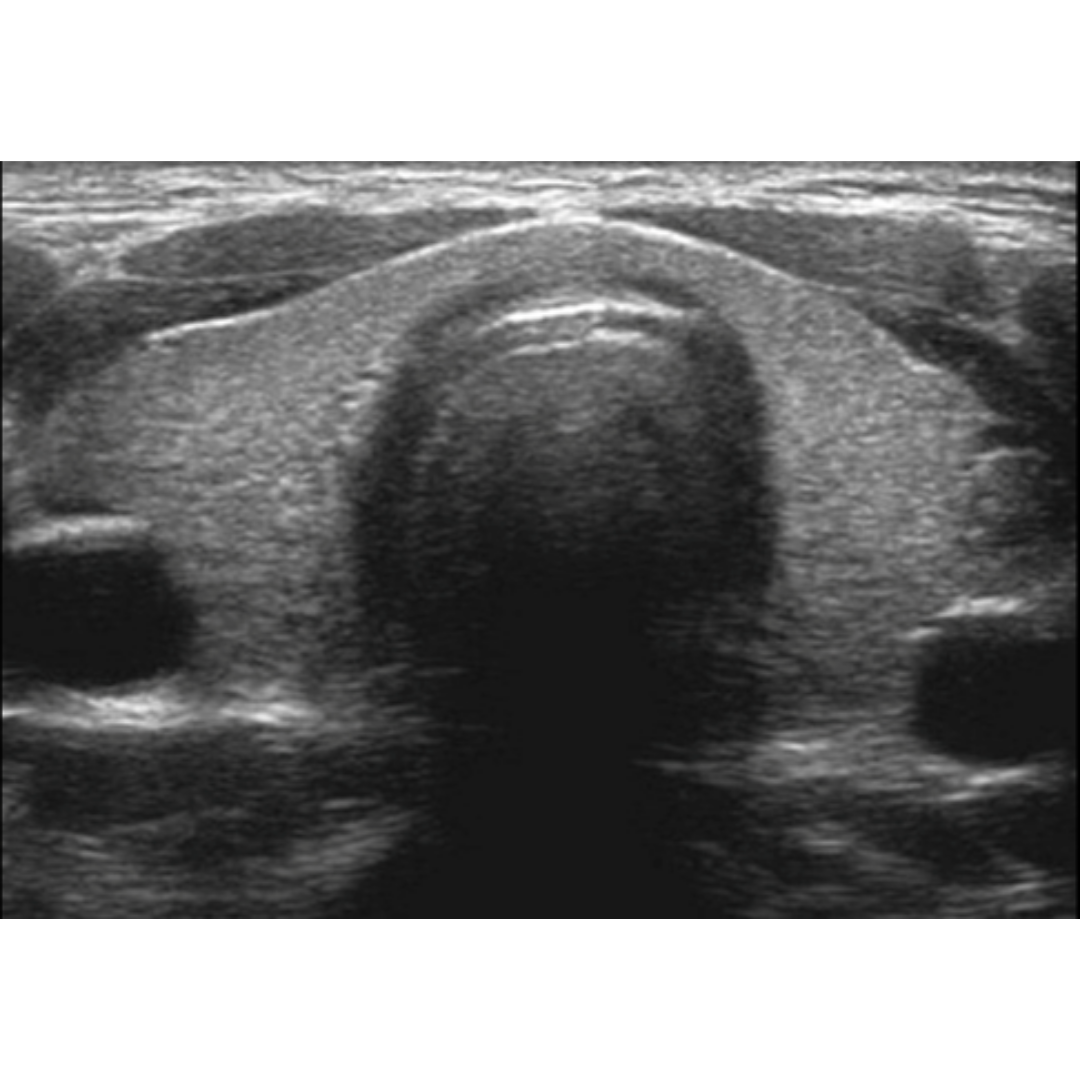

Figura 3. Adenoma paratiroideo superior izquierdo. Exploraciones longitudinales (A) y transversales (B). El parénquima tiroideo adyacente se observa hipoecogénico, heterogéneo como resultado de tiroiditis crónica autoinmune.